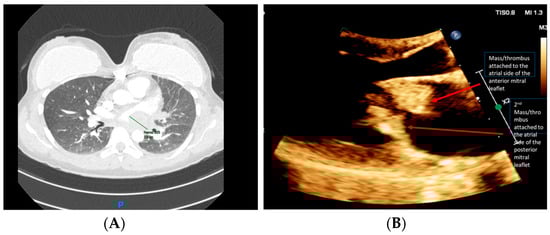

A chest computed tomography angiography (CTA) was performed, which did not demonstrate evidence of PE. The imaging revealed a large left atrial (LA) filling defect, with signs of pulmonary hypertension (Figure 2A). Transthoracic echocardiogram (TTE) demonstrated multiple mobile mitral valve masses (anterior and posterior), mostly on the atrial side, 29 × 16 mm in size, prolapsing into the left ventricle (LV) and causing severe functional mitral stenosis (MS), mitral regurgitation (MR), and pulmonary hypertension (Figure 2B).

Figure 2. (A) Chest CT revealed a large filling defect extending from the left atrium to the left hilum; and (B) TTE (parasternal long axis) demonstrated multiple mobile masses attached to the mitral valve. Published with the permission of the rights owner.